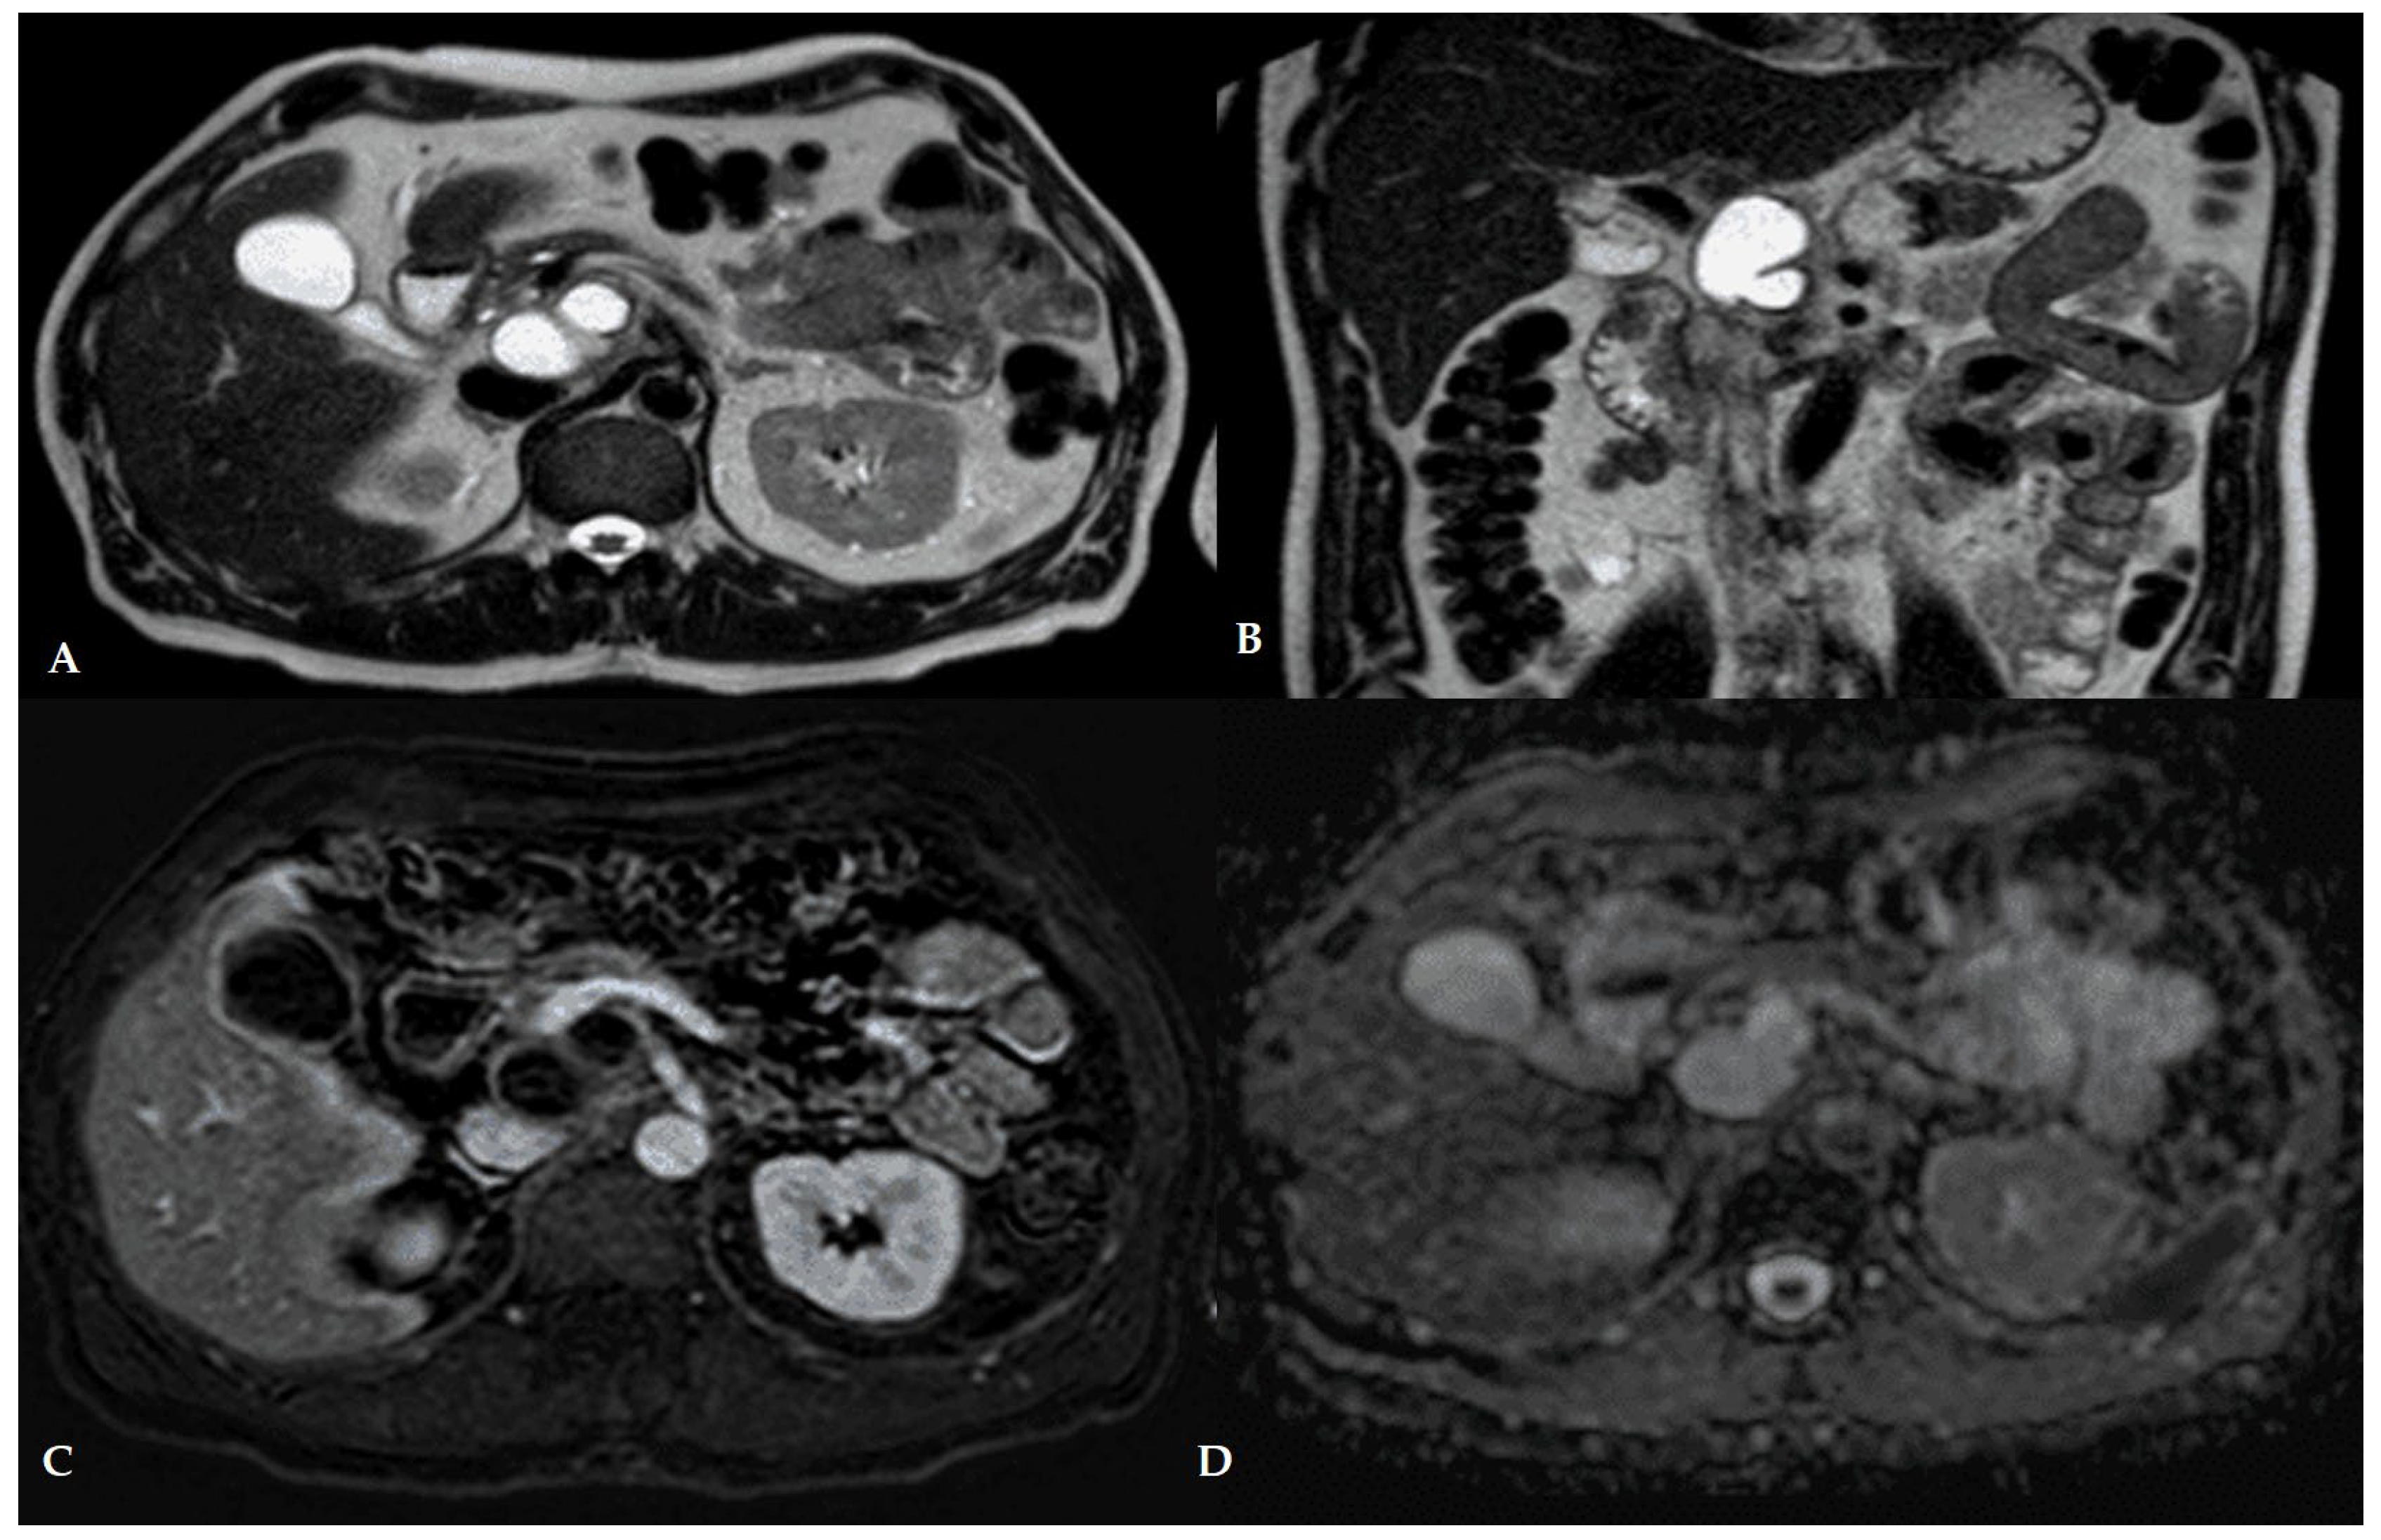

4.2. Role of Magnetic Resonance Imaging

| Sequence | Purpose/Diagnostic Value |

| T2-weighted (axial and coronal, ±fat-sat) | Depicts fluid as high signal intensity (bright). Detects internal septations or debris as low-signal (dark) areas within fluid. Fat-suppressed T2 helps distinguish fluid from fat; necrotic fat remains hypointense on fat-sat T2. |

| MR Cholangiopancreatography (MRCP) | Heavily T2-weighted sequences optimized to visualize pancreatic and biliary ducts. Demonstrates ductal anatomy, communication between collections and the pancreatic duct, duct leaks, disconnected duct syndrome, or obstructive calculi. |

| T1-weighted (unenhanced) | Simple fluid appears hypointense (dark). Proteinaceous or hemorrhagic fluid shows intermediate to high signal. Useful for differentiating fluid composition. |

| Dynamic contrast-enhanced T1 (3D fat-sat GRE, arterial/portal/delayed phases) | Evaluates wall enhancement, internal septa, or solid components. Pseudocysts typically show thin rim enhancement, whereas WON walls are thicker. Non-enhancing internal material confirms necrotic debris. |

| Fat-saturated T1 (post-contrast) | Improves detection of subtle wall enhancement and hemorrhage. The fibrous capsule of mature collections usually enhances on delayed phases. |

| Diffusion-Weighted Imaging (DWI) (optional) | Identifies viscous/cellular debris and may suggest infection. Restricted diffusion (high DWI signal, low ADC) can correlate with infected or proteinaceous necrosis. Still emerging but complements CT signs (e.g., gas). |